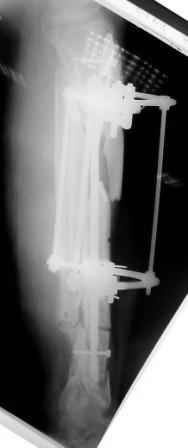

Коллеги!Позвольте продолжить обсуждение темы «ложный сустав левой голени.» Больной К 45 лет, начало см. http://www.weborto.net/forum/1228422607/ И рассказать о результатах проделанной работы. Остановились на следующей тактике 1) Наложить Аппарат Илизарова. В аппарате восстановить оси трех смещенных относительно друг-друга фрагментов большеберцовой кости. Устранить вальгусную деформацию дистального отдела большеберцовой кости. Что и было выполнено. - Была выполнена репозиция в аппарате (рис1) 2) После репозиции более очевидна стала проблема дефекта кости в верхней трети голени, два фрагмента свободно лежат. Остановились на варианте перехода на интрамедуллярный синтез стержнем с покрытием костный цемент+ванкомимцин и замещении дефекта с помощью транспорта фрагмента (рис 2) 3) Третьим этапом наложили модуль на промежуточный фрагмент.(рис 3) И начали его транспорт на стержне в проксимальном направлении. (рис 3 а) Надеемся что «вырастет» регенерат в дистальном отделе, а в проксимальном отделе фрагмент «упрется» и прирастет. Хочу сказать слова благодарности за обсуждение на форуме этого случая. Особые слова благодарности Иванову Павлу Анатольевичу!!! Он помогал Словом, а самое главное делом. Приезжал, оперировал! За что ему нижайший поклон! С ув Коробушкин Г

Меня расстраивает значительное вальгусное смещение проксимального отломка большеберцовой кости. Оно очень значительное. Рассверливание

костно-мозгового канала во время операции было непростым, и за время его проведения канал в проксимальном отломке образовался избыточным по

диаметру. Это в определенной мере способствовало образованию данного смещения. Жаль, что в конце операции мы недооценили его степень, иначе

бы устранили его при помощи винта-поллера. Может быть, участники Ортофорума что-либо посоветуют по этому поводу. Стоит ли как-то попытаться исправить ситуацию?